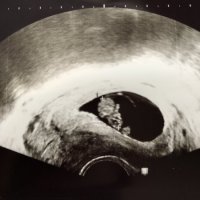

Ultralyd i dag 14+0 ❤